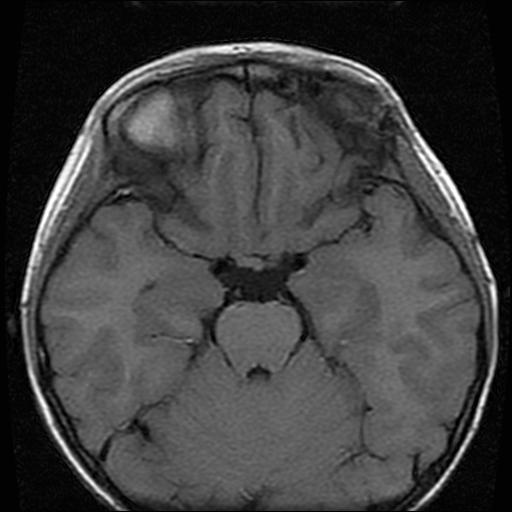

6岁小儿,左侧视神经瘤术后。现左侧视力减退。